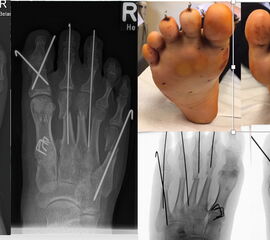

Abb. 3 a-j: Beispiel einer Calcaneusverschiebeosteotomie mit offenen Wachstumsfugen und der entsprechenden Osteosynthese mit Kirschner Drähten. Lokalisation der Osteotomie (a), Lage der Fräse (b-d), Drahtlage mehrere Ansichten (e-h), Heilung der Osteotomie 4 Wochen postoperativ und Entfernung der Drähte (i-j).

Calcaneus-Osteotomie

Die minimalinvasive Calcaneusverschiebeosteotomie bietet eindeutige Vorteile gegenüber dem offenen Verfahren, sodass wir bei Kindern und Jugendlichen nahezu keine offene Verschiebeosteotomie mehr durchführen. Am Calcaneus liegt die offene Wachstumsfuge dorsal. Bei der Durchführung müssen Schenkel der V-förmigen Osteotomie daher etwas steiler angelegt werden, in einem stumpfen Winkel (siehe Abb. 3 a-j). Für die Osteotomie liegen unsere Patienten auf dem Rücken und der BV wird für die exakte Seitaufnahme eingestellt. Der Fuß lagert auf einem hohen OP-Kissen und die Osteotomie kann bequem mit einem langen Kirschner-Draht und einem sterilen Stift angezeichnet werden (Abb. 15).